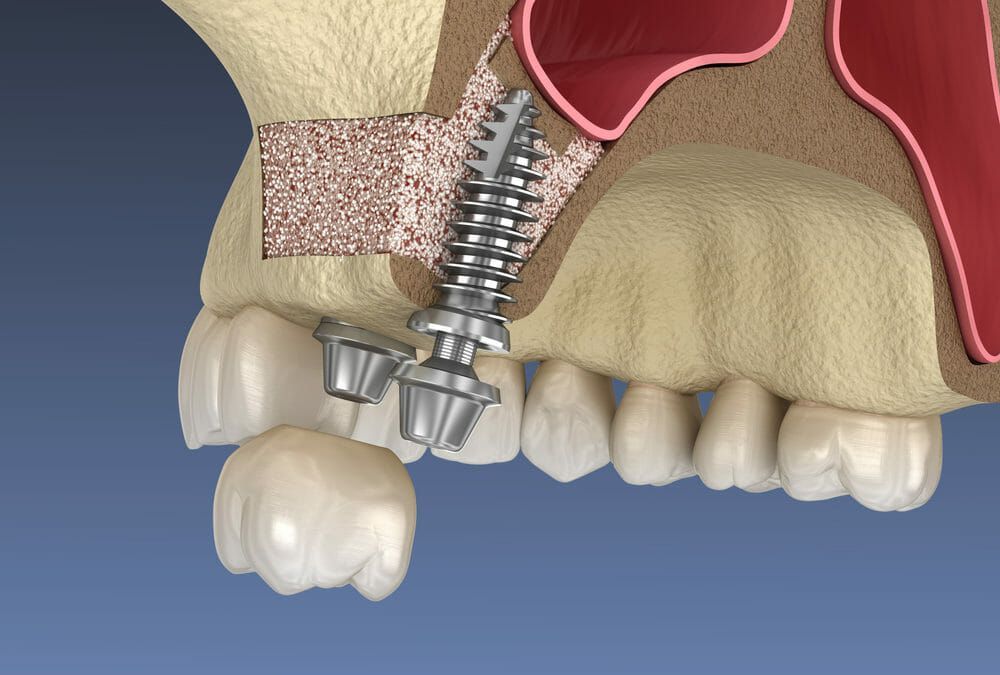

Lateral sinus lift is the gold standard for significant bone augmentation in the upper jaw. Through a small window in the side of the jawbone, we gently lift the sinus membrane and add bone grafting material to create adequate height for implant placement.

Lateral sinus lift approaches from the side of the jawbone and can add significant bone height (5-15mm). It's used for multiple implants or severe bone deficiency. Crestal sinus lift goes through the implant site and adds modest height (3-5mm). It's less invasive but suitable only for single implants with mild bone deficiency.